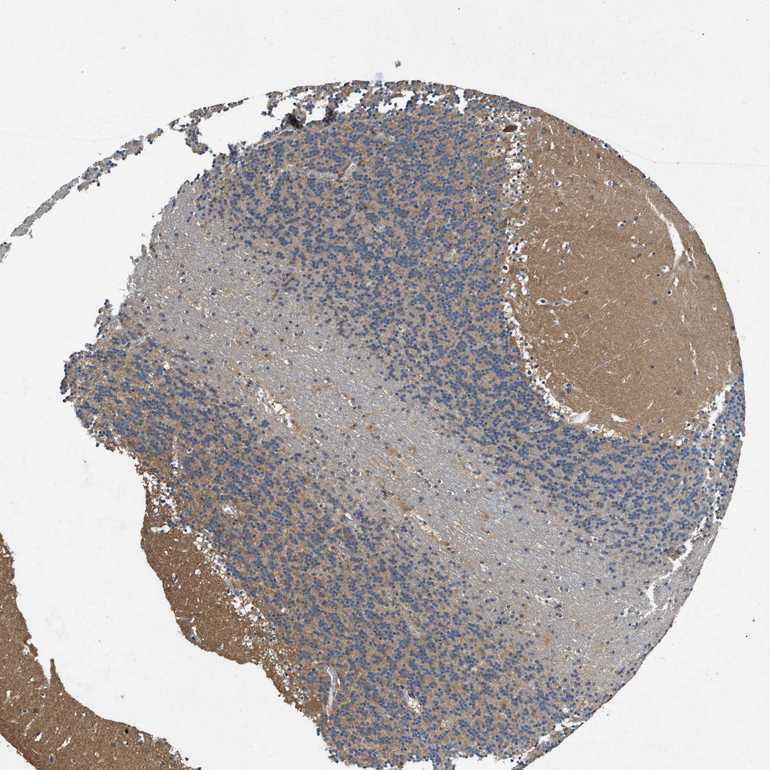

BRAIN CEREBELLUM Show tissue menu

CEREBELLUM - Expression summary

CEREBELLUM - Antibody stainingi

Antibody staining in the annotated cell types in the current human tissue is reported as not detected, low, medium, or high, based on conventional immunohistochemistry profiling in selected tissues. This score is based on the combination of the staining intensity and fraction of stained cells.

Each image is clickable and will lead to virtual microscopy that enables deeper exploration of all samples and also displays staining intensity scores, fraction scores and subcellular localization as well as patient and tissue information for each sample.

Antibody HPA017336Antibody CAB069423

Purkinje cells MediumMedium

Cells in granular layer MediumMedium

Cells in molecular layer MediumLow